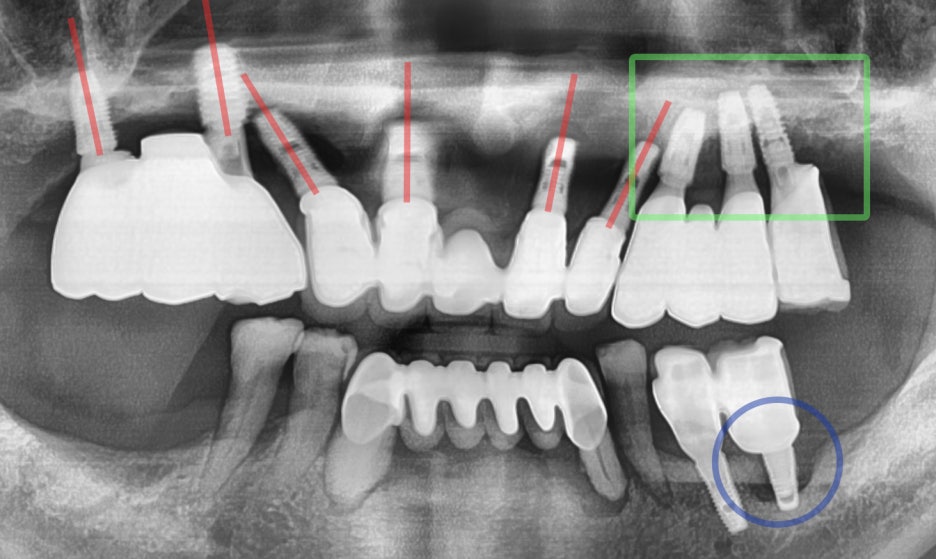

먼저 잘못 된 예시를 보여드립니다.

먼저, 확인해야 될 포인트는 식립 기울기 입니다.

빨간색으로 표시를 해둔 것은, 기울기인데

다 표시를 하진 않았습니다.. 너무 많아서.

여하튼, 각도들 자체가 일률적이지 않고

다 서로 다른 방향을 바라보고 있습니다.

그쵸?

물론, 파노라마 엑스레이 자체가

왜곡이 많은 것은 사실이나 왜곡이 많은데도

이 정도의 기울기를 보여준다면 사실 진짜

엉터리라는 거…

환자의 구강 상태에 맞게, 뼈의 두께나

교합 관계에 의거하여 알맞은 각도로 심어야

되는데 이 엑스레이를 기준으로 말씀드리면

그런 것들을 전혀 고려하질 않았다는 것으로

간주 할 수 있겠습니다.

게다가, 초록색으로 표기 된 곳들을 보면

임플란트의 끝 쪽이 모여 있는 것을 볼 수 있죠?

우리, 치조골… 즉 뼈는 피가 지나다닙니다.

근데, 저렇게 한 곳으로 모아서 심게 되면

혈액 순환도 잘 되지 않을 뿐더러 추후

골파괴(Bone defect) 등의 현상이 나타날

가능성이 농후합니다.

아울러, 파란색으로 표기를 해 둔 곳은

이미… 임플란트 주위염(Peri-implant)가

나타나 있는 곳입니다.

보철의 형태 불량(Emergency profile)에

따라 음식 저류가 나타났으며, 올바르게 관리가

되지 않았기 때문에 나타난것으로 소견 되네요.